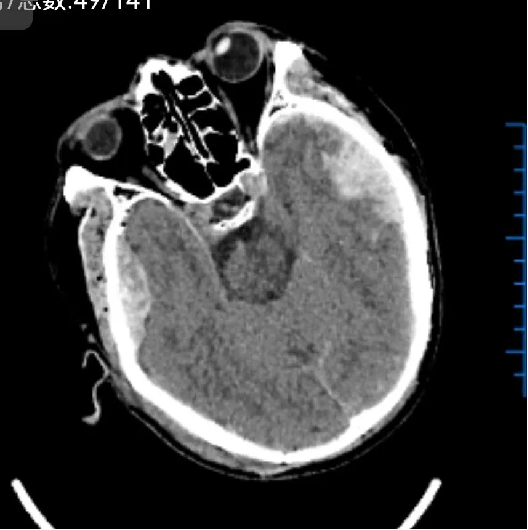

术后: